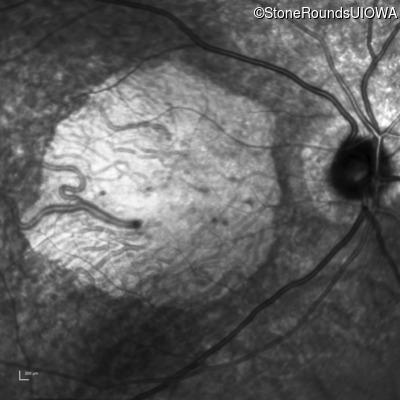

AR Stargardt Disease (IIA)

Age at visit:

74 years

OD

OS

20/160 +2 sc

20/160 sc

AR Stargardt Disease

ABCA4

Gly607Arg GGG>AGG

IVS30+1321 A>G

AR